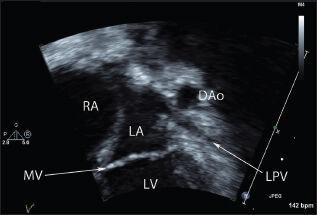

This is a case report of a patient with Trisomy 21 with Ebstein anomaly, a ventricular septal defect, and acquired pulmonary vein stenosis; a rare combination, diagnosed during a routine neonatal examination.

这是一份关于一名患有21三体综合征合并埃布斯坦畸形、室间隔缺损和后天性肺静脉狭窄患者的病例报告,这种罕见的组合在常规新生儿检查中被诊断出来。